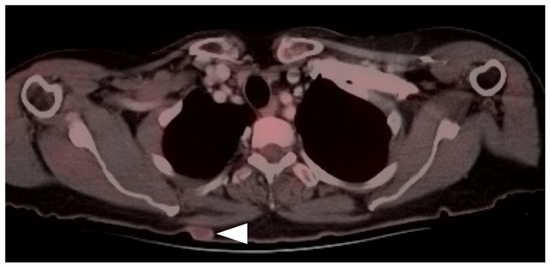

- Falch, C.; Mueller, S.; Kirschniak, A.; Braun, M.; Koenigsrainer, A.; Klumpp, B. Anorectal malignant melanoma: Curative abdominoperineal resection: Patient selection with 18F-FDG-PET/CT. World J. Surg. Oncol. 2016, 14, 185. [Google Scholar] [CrossRef] [Green Version]